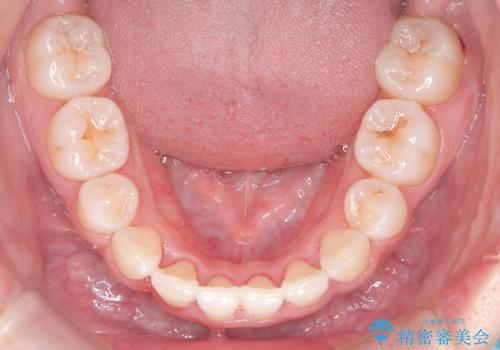

八重歯を改善!美しい口元を実現するハーフリンガル矯正

- 前歯のガタツキと口元のコンプレックスを解消するために来院されました。

ハーフリンガル矯正は、見た目を気にせずに矯正治療ができる方法です。この治療法は、八重歯や前歯のガタツキを効果的に改善します。特徴として、ワイヤーが上の歯の裏側に装着されるため、装置が外から見えません。これにより、治療中も自然な笑顔を保ちながら安心して治療を続けることができます。歯並びの悩みを持つ方にとって、非常に魅力的な選択肢です。

- 矯正治療後の保定が不十分だと後戻り(元の位置に戻ろうとする動き)をします